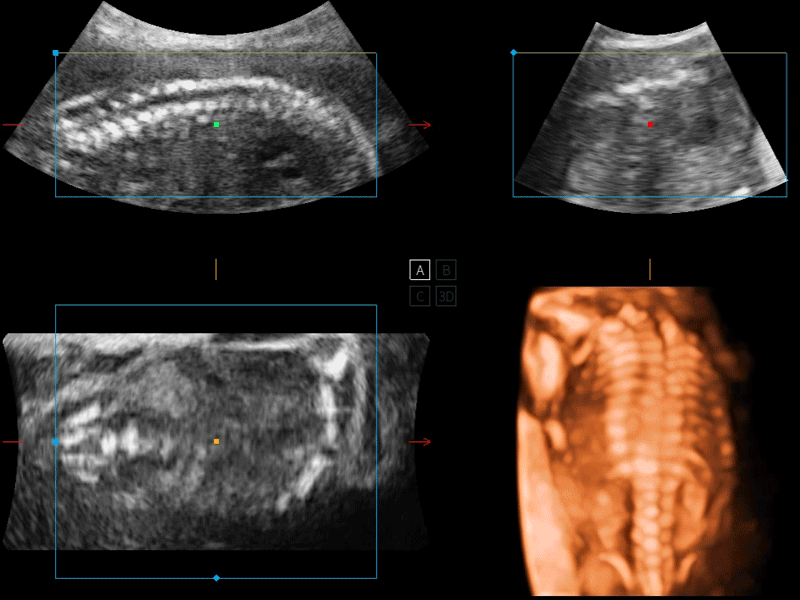

S-Fetus 产科扫查助手

S-Fetus基于大数据深度学习算法,能够帮助您在产前筛查过程中智能识别胎儿标准切面、自动测量并录入报告。一个按键,即可智能、精准、高效地获取胎儿生理指标,极大简化您的产科检查操作。